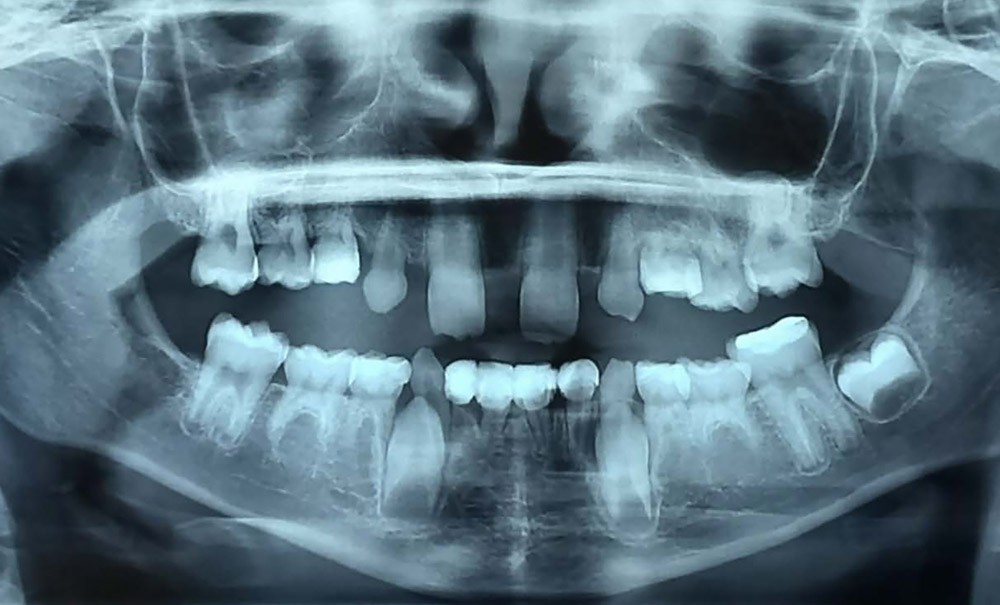

Cliniquement, une dent atteinte d’infraclusion est positionnée sous le plan d’occlusion par rapport aux dents adjacentes. La classification de Brearley permet de distinguer 3 stades d’infraclusion : légère (1 mm en dessous du plan d’occlusion), modérée (table occlusale positionnée au niveau du point de contact dentaire d’une des deux dents adjacentes), sévère (table occlusale située au niveau gingival proximal ou en dessous)(fig.